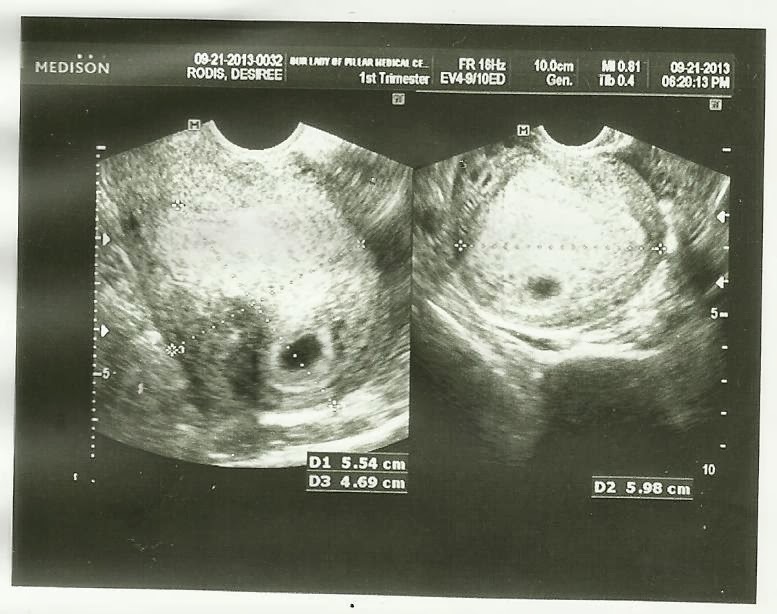

And then its time for our first ultrasound. And boy, oh boy, we were excited!

| Our first glance to our baby! :-) |

I know it still showed nothing, just a gestational sac and tiny yolk sac. I had ultrasound din to check if may problem sa uterus and ovary ko. Or they can check din if possible ectopic pregnancy. The doctor couldn't detect a heart beat at that time. She said it was just too small and that I should come back in a week or two. She also said everything appeared to be developing normally and I looked more like I was in my fifth week not 6 weeks. So yehey!!! The Husband and I were very happy.